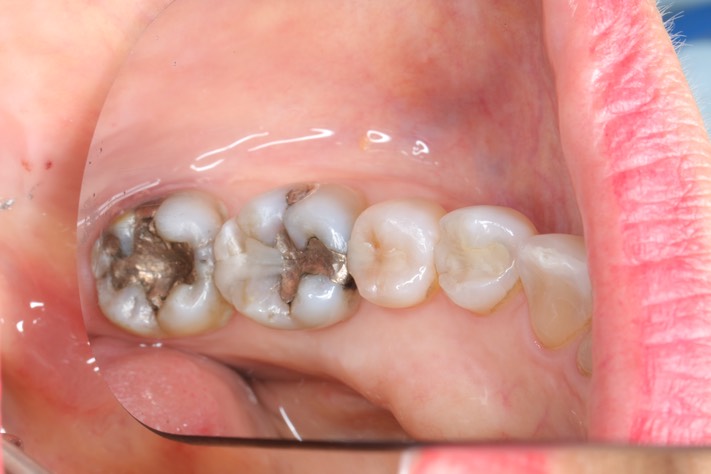

Gary Umeda #30 pre-op